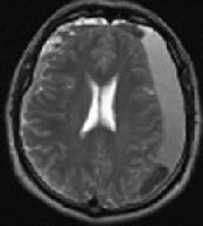

МРТ головного мозга. Аксиальная МРТ типа FLAIR. Аневризма и САК, внутрижелудочковое кровоизлияние.